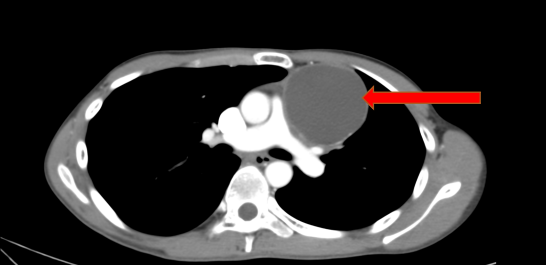

这名19岁少年是刚入学的大一新生,在学校组织体检中,胸透检查提示“前纵膈区域异常密度影”,随后至佛山市第一人民医院胸外科进一步检查。经胸部增强CT详细评估,医生发现其前纵膈位置存在一个大小约10cm的占位性病变,肿瘤内部可见脂肪密度影与钙化灶,结合肿瘤标志物(AFP、β-HCG)检测结果正常,初步诊断为“良性前纵膈畸胎瘤”。

第一步:影像学先定位、猜性质

最常用的是胸部 CT,能清晰看到肿瘤的位置、大小,还能通过 “特殊信号” 初步判断 —— 比如看到 “黑色的脂肪影”“白色的钙化点(可能是牙齿 / 骨骼)”,大概率就是畸胎瘤。胸片可初步筛查,但细节看不清;MRI 则能进一步看肿瘤是否侵犯心脏、大血管,帮医生制定手术方案。